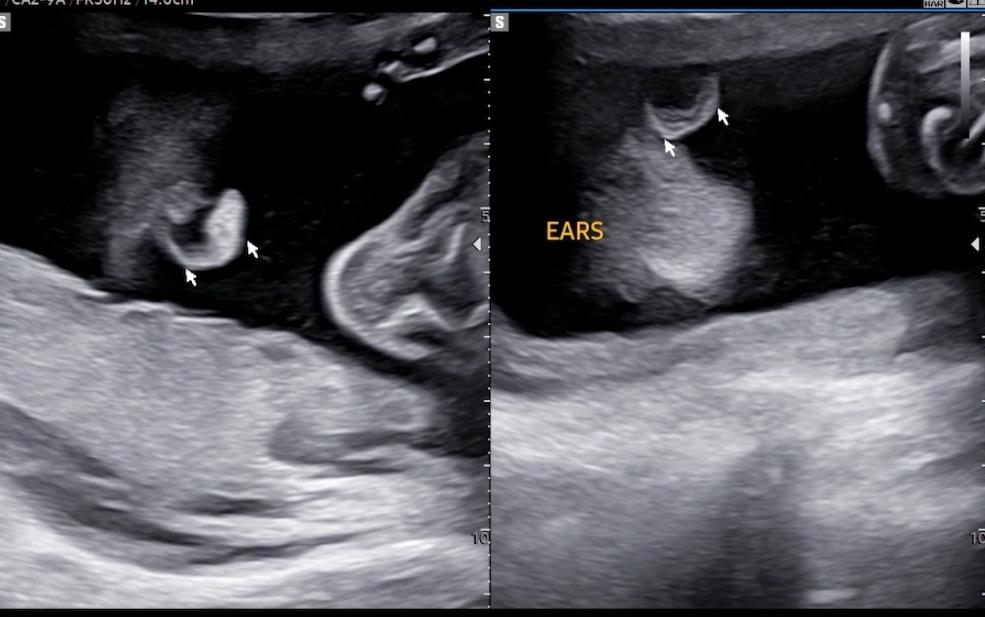

양쪽 귀도 확인했어요.